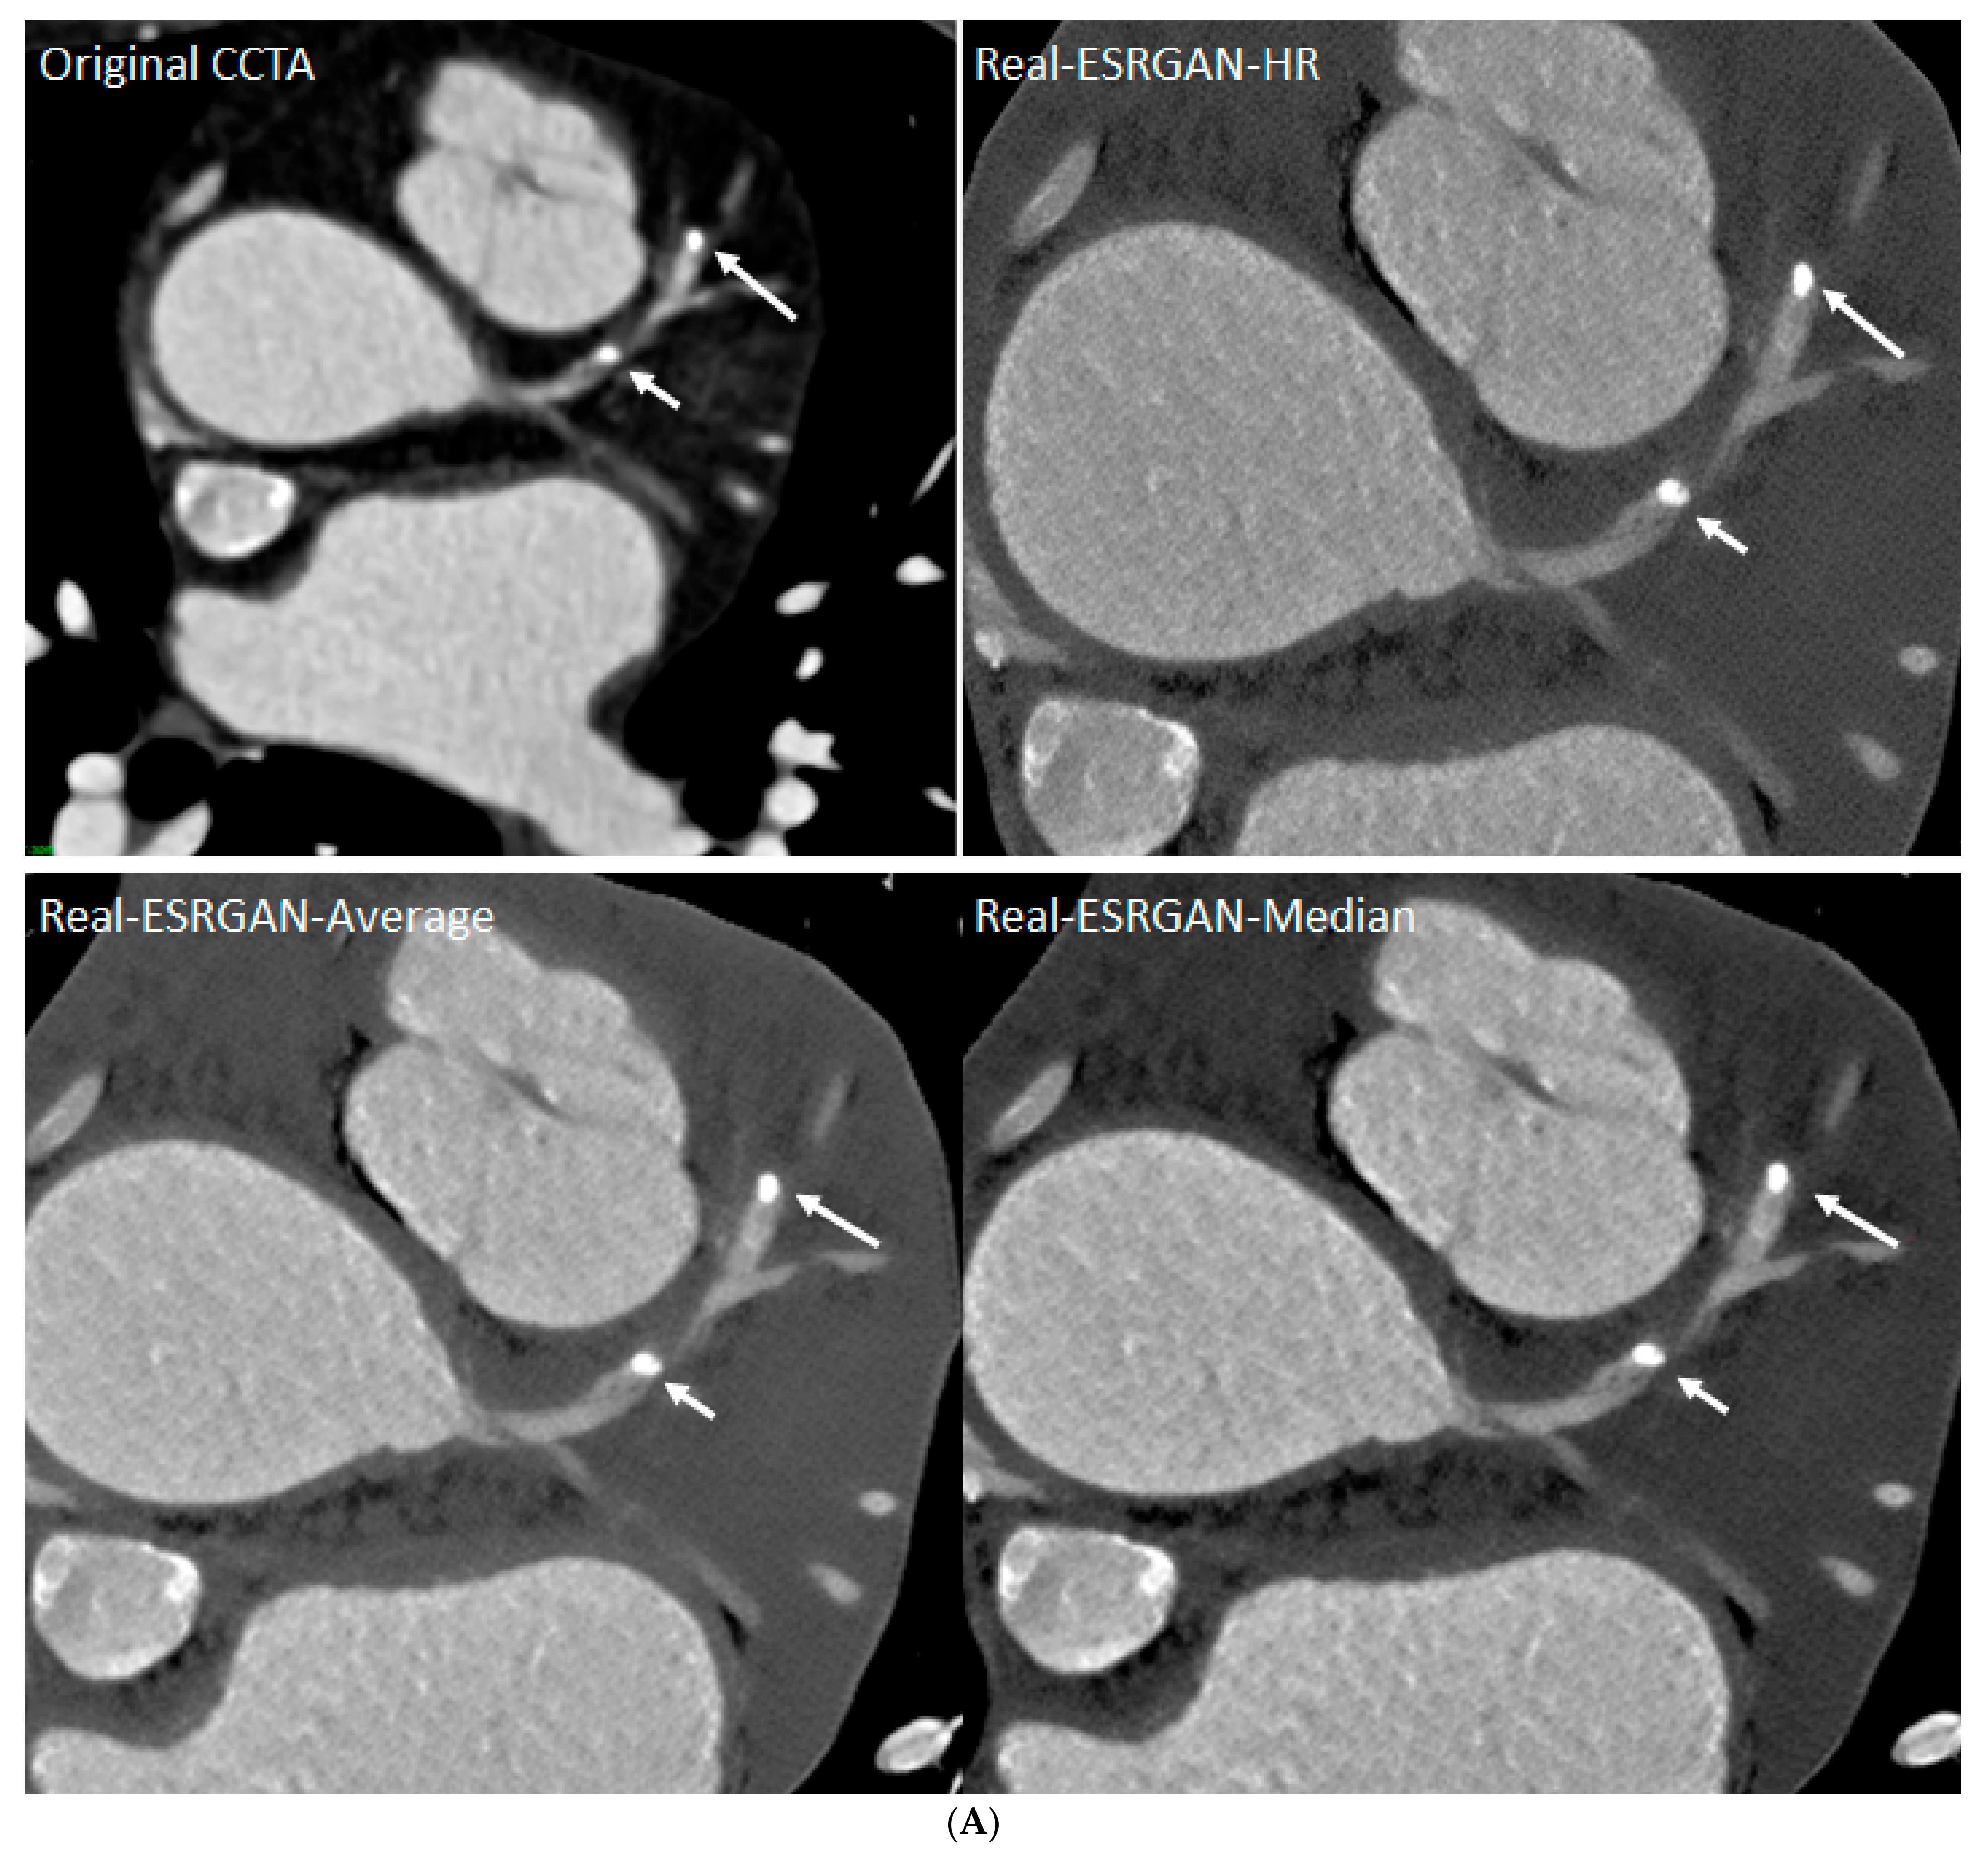

- Sun, Z.; Ng, C.K. Artificial intelligence (enhanced super-resolution generative adversarial network) for calcium deblooming in coronary computed tomography angiography: A feasibility study. Diagnostics 2022, 12, 991. [Google Scholar] [CrossRef]

- Sun, Z.; Ng, C.K. Finetuned super-resolution generative adversarial network (artificial intelligence) model for calcium deblooming in coronary computed tomography angiography. J. Pers. Med. 2022, 12, 1354. [Google Scholar] [CrossRef]